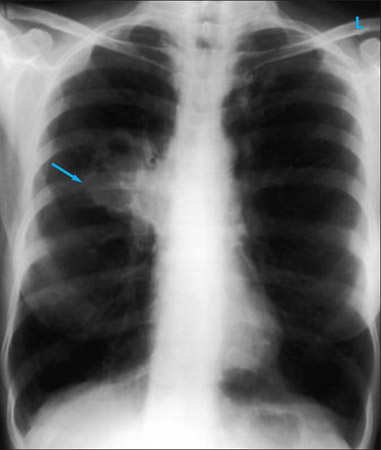

Uma radiografia torácica deve ser obtida no início da avaliação da tosse crônica.[38] Embora não seja diagnóstica das causas mais comuns, os achados podem facilmente desviar a avaliação para causas de maior gravidade como doenças pulmonares estruturais. Eles incluem câncer pulmonar, fibrose pulmonar, tuberculose, bronquiectasia, pneumonia, aspiração e sarcoidose.[Figure caption and citation for the preceding image starts]: Radiografia torácica mostrando hiperinsuflação em paciente com DPOC. A hiperinsuflação é causada pelo componente de enfisema na DPOC, em vez da bronquite crônica subjacente aos sintomas da tosseDo acervo pessoal do Dr. M. A. Sharifabadand, SUNY na Stony Brook School of Medicine, Departamento de Medicina Pulmonar e Intensiva, Mineola, Nova York, e Dr. J. P. Parsons, The Ohio State University Medical Center, Columbus; usado com permissão [Citation ends].

[Figure caption and citation for the preceding image starts]: Radiografia torácica mostrando múltiplas metástases pulmonares miliares (setas). O tumor primário era carcinoma de tireoideE. Dick, Student BMJ. 2001;9:10-12 [Citation ends].